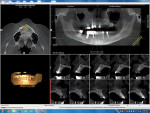

A preoperative CBCT scan (i-CAT, Imaging Sciences International, LLC, www.i-cat.com) was taken to help determine the potential positioning of dental implants and evaluate the significant anatomy, such as the maxillary sinus, as well as the horizontal and vertical bone available (Figure 1). Per the diagnosis, the remaining maxillary teeth were scheduled to be surgically and atraumatically removed, and immediate implants were to be placed. Immediately following extraction of the remaining maxillary teeth, an immediate complete denture was fabricated and seated (Figure 2).

Figure 3 illustrates the CT diagnosis and proper positioning of six maxillary dental implants within the viability of the existing anatomy using software (Invivo 5, Anatomage Dental, www.anatomage.com). Implants (3.7-mm diameter Glidewell Inclusive tapered implants) were strategically placed essentially parallel and away from the sinus areas in the edentulous maxilla as determined by CT planning. A surgical guide was created to allow for initial depth determination. Subsequent increase in diameter of the surgical burs created the osteotomy site for the implants. For this patient, implants were positioned in the edentulous areas of position Nos. 4 through 6 and 11 through 13. They were torqued to 25 Ncm, flat cover screws were placed, and the existing maxillary conventional complete denture was seated. A Mucopren® Soft liner (Kettenbach, www.kettenbach.com) was used to condition the tissue during the 4-month integration period.